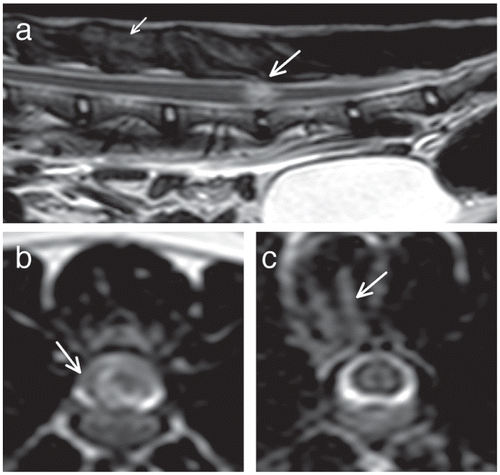

Изобр 1 (a) Сагиттальные T2-взвешенные и (b) поперечные T2- взвешенные изображения на уровне L5–L6 межпозвоночных дисковых пространств, и (c) тело позвонка L4 египетской мау в возрасте 2 года и 9 месяцев (кошка 2). (a) Фокальная внутрипаренхимальная гиперинтенсивность имеется на уровне L5–L6 межпозвоночного дискового пространства (длинная стрелка). Хотя пульпозное ядро имеет сниженный обьем, в сравнении с соседним диском, у него сохраняется гомогенный гиперинтенсивный сигнал. (b) Небольшое количество постороннего материала имеется в эпидуральном пространстве (стрелка). (a,c) Плохо отграниченная гиперинтенсивность в пределах эпаксиальной мускулатуры на уровне тела позвонка L4, что наводит на мысль о контузии эпаксиальной мускулатуры, отеке или геморрагии, рассматривалась показательной для наружной травмы (короткая стрелка [a] и стрелка [c]).

МРТ выявило ANNPEлокализованную на уровне C3–C4 (n = 1), T12–T13 (n = 1), T13–L1 (n = 1), L1–L2 (n = 1), L3–L4 (n = 3), L4–L5 (n = 1) и L5–L6 межпозвозвоночных дисковых пространств (n = 3). Одна кошка имела перелом дорсального остистого отростка L7 позвонка, который не был ассоциирован ни с нейроанатомической локализацией, ни с анатомической локализацией ANNPE и, поэтому, рассматривался как случайный. Имелось доказательство патологической T2- взвешенной гиперинтенсивности в пределах эпаксиальной мускулатуры, в сравнении с окружающей мускулатурой, наводя на мысль о контузии, геморрагии или отеке у 5 кошек (Изобр 1с). Из этих 5 кошек 2 кошки не имели историю или находки исследования, совместимые с травмой, в то время, как другие 3 кошки имели подтверждение травмы свидетелями.